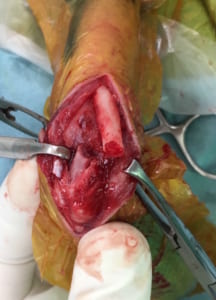

症例2:チワワ、2歳齢、抱っこしていたら飛び降りてしまい、キャンと鳴いて右前肢挙上。

術前X線画像:右橈尺骨遠位端骨折

手術所見:TITAN LOCK T字プレートによる整復・固定